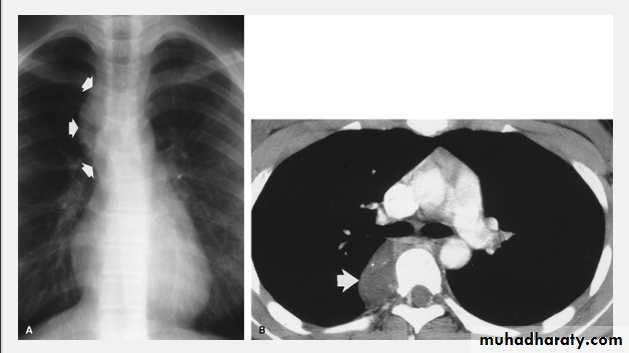

On a posteroanterior chest x-ray (A), the left hemithorax is very dark or lucent because the left lung has collapsed completely (white arrows).The tension pneumothorax can be identified because the mediastinal contents, including the heart, are shifted toward the right, and the left hemidiaphragm is flattened and depressed. A computed tomography scan done on a different patient with a tension pneumothorax (B) shows a completely collapsed right lung (arrows) and shift of the mediastinal contents to the left.

Tension Pneumothorax. Portable chest film in a 43-year-old woman with ARDS shows a large right pneumothorax with mediastinal shift and ipsilateral diaphragmatic depression, suggesting tension.

Air was evacuated under pressure during emergent placement of a right chest tube.